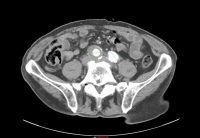

Ejemplo de película:

- AAA infrarrenal, diámetro 54,2 mm

- Aneurisma de la A. iliaca communis derecha, diámetro 41,1 mm